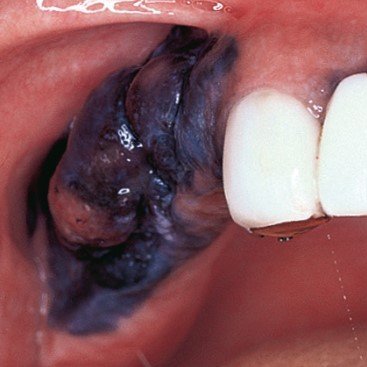

Oral cancer is a serious condition that affects various parts of the mouth. Here are the warning signs to watch out for:

Oral cancer, additionally referred to as mouth cancer, is commonest amongst the head and neck cancers. As per statistics, carcinoma develops in 10.5 adults per one 100,000 population. The foremost common causes embrace a mixture of excessive smoking and alcoholic abuse. The commonest sign of developing carcinoma is ulceration that doesn’t heal within a fortnight. The key to successfully treat carcinoma is its timely detection and treatment.